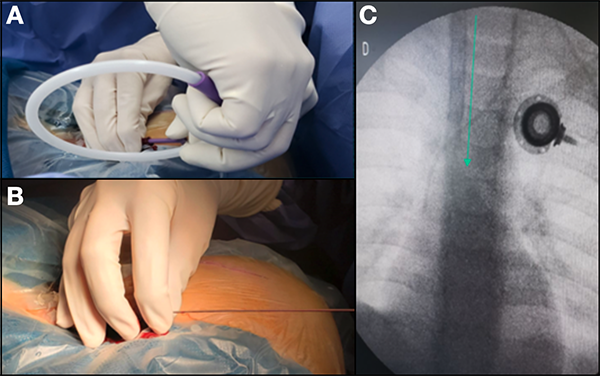

Se aplica la técnica de “Seldinger” modificada para el acceso percutáneo venoso. Habitualmente contamos con la colaboración de los cirujanos generales para este paso. Recomendamos usar ecógrafo con transductor de superficie para localizar el paquete vascular del cuello. La vena yugular interna derecha es de elección dado que por su disposición anatómica se llega de manera más directa a la aurícula derecha. Topográficamente la encontramos en el extremo superior de la fosa supraclavicular menor (sitio de convergencia de los fascículos esternal y clavicular del esternocleidomastoideo). Utilizamos la aguja que contiene el set o un “catéter corto sobre aguja”, tipo Abbocath 18 G, conectado a una jeringa de 10 ml que contiene 5cc de solución fisiológica. Cuando se identifica el vaso mediante ecografía, punzamos con una inclinación de 45 grados a la superficie cutánea y, aspirando suavemente con la jeringa, debe verse la salida de sangre oscura (venosa) una vez alcanzada la luz de la vena. Durante esta maniobra la aguja se visualiza en el ecógrafo, lo que permite ir corrigiendo la orientación de esta (Figura 1).

Figura 1: A) Con el transductor ecográfico iniciamos el barrido. Lo apoyamos a nivel del tercio inferior del músculo esternocleidomastoideo y lo llevamos hacia arriba. Nótese la angulación de la aguja para la punción. B) Visión ecográfica: al comprimir suavemente con el transductor, la vena yugular es fácilmente colapsable (lo que permite identificarla) a diferencia de la carótida que no sufre modificaciones ante esta maniobra.

Se desconecta la jeringa (el retorno de sangre no debe ser pulsátil) y se introduce la cuerda jota a través de la aguja de punción. Se efectúa control radioscópico para asegurarnos la ubicación de la guía metálica a nivel de la vena cava superior y posteriormente se retira el punzante inicial (Figura 2).

Figura 2: A) Realizada la punción y comprobando que hay retorno de sangre venosa, progresamos la cuerda jota. B) Retiramos la aguja inicial y comprimimos el punto de entrada de la guía. C) En la visión radioscópica ilustramos con una flecha verde paralela y a la derecha de la cuerda metálica. En esta imagen se observa un catéter venoso implantable utilizado para tratamiento quimioterápico que drena en la unión cavoatrial a la altura de la carina, sitio elegido para nuestra derivación. Su ingreso es contralateral, por lo que su presencia, o la de otras vías centrales no contraindica el procedimiento. Puede optarse colocar la derivación homolateral a un acceso central existente, siendo el sitio de punción más conveniente, una vena distinta a la elegida en el primer acceso. Figura 2. A) Realizada la punción y comprobando que hay retorno de sangre venosa, progresamos la cuerda jota. B) Retiramos la aguja inicial y comprimimos el punto de entrada de la guía. C) En la visión radioscópica ilustramos con una flecha verde paralela y a la derecha de la cuerda metálica. En esta imagen se observa un catéter venoso implantable utilizado para tratamiento quimioterápico que drena en la unión cavoatrial a la altura de la carina, sitio elegido para nuestra derivación. Su ingreso es contralateral, por lo que su presencia, o la de otras vías centrales no contraindica el procedimiento. Puede optarse colocar la derivación homolateral a un acceso central existente, siendo el sitio de punción más conveniente, una vena distinta a la elegida en el primer acceso.

Se realiza una pequeña incisión con bisturí N°11 e introducimos el dilatador de 7 French (Fr) enhebrando la cuerda jota. Reinsertamos el dilatador montado a la vaina desprendible de 8 Fr que nos permitirá la introducción del catéter distal. Cabe señalar que existen dos tipos de catéteres: unos completamente revestidos en bario que los hace radiopacos, y otros transparentes que cuentan solamente con una delgada línea “baritada” difícil de ver bajo radioscopia. En este caso se aconseja llenarlo con contraste hidrosoluble para su mejor visualización (Figura 3). En el extremo distal del catéter intravascular deben hallarse todas las hendiduras íntegras y permeables. Realizamos la medición aproximada de la longitud del catéter a introducir; para esto, el punto de referencia a tomar es el tercer cartílago costal sobre el borde esternal, ligeramente por encima del nivel de la mamila. Buscamos marcar lo que denominaremos punto venoso inferior, que se corresponde a nivel interno con la unión cavoatrial (entrada a la aurícula derecha). El catéter debe encontrarse purgado y el extremo proximal debe conectarse a una jeringa cargada con solución fisiológica.

Figura 3: A) Sobre la cuerda jota realizamos una mínima incisión con bisturí N° 11. Durante el pasaje del dilatador con la vaina descartable no debemos encontrar resistencia y la progresión al final debe acompañarse de movimientos rotatorios que facilitarán el ingreso. B) Etiqueta correspondiente al set que contiene el introductor Peel-Away 8 French. Este tamaño es el que nos permitirá la progresión del catéter distal, cuyo diámetro es de 2.2 mm.

Se sostiene con pinza de punta roma el sistema introductor y retiramos el dilatador simultáneamente a la cuerda J. Saldrá sangre inmediatamente por lo que la maniobra de introducción del catéter debe ser rápida (Figura 4). Se debe progresar tantos centímetros como los estimados en la medición previa de superficie. En este paso se solicita la atención del anestesiólogo, ya que el monitor acusa latidos ectópicos en caso de habernos pasado del lugar indicado. Se repite el control radiológico para asegurar que la punta se localice en el punto venoso inferior. En la imagen debe verse la punta del catéter a la altura de la carina.

Figura 4: A) Momento donde se introduce el catéter distal. La cuerda eventualmente puede dejarse, sirviendo de guía cuando el procedimiento se hace dificultoso.